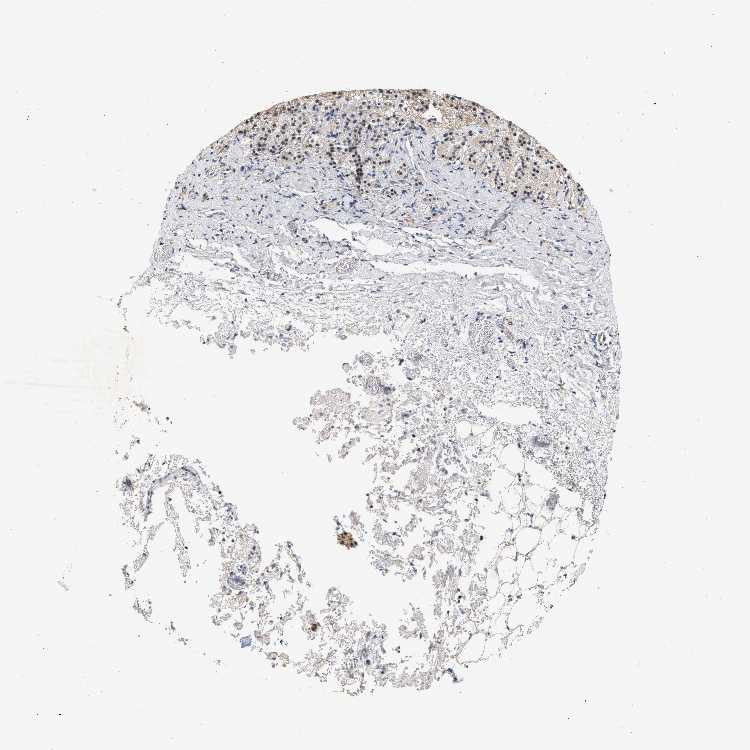

ADRENAL GLAND - Antibody stainingi

Antibody staining in the annotated cell types in the current human tissue is reported as not detected, low, medium, or high, based on conventional immunohistochemistry profiling in selected tissues. This score is based on the combination of the staining intensity and fraction of stained cells.

Each image is clickable and will lead to virtual microscopy that enables deeper exploration of all samples and also displays staining intensity scores, fraction scores and subcellular localization as well as patient and tissue information for each sample.

Antibody HPA019096Antibody HPA019687

Glandular cells LowLow